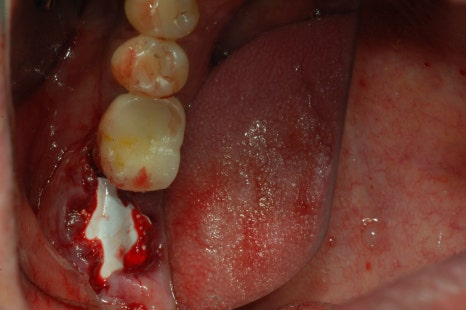

그 과정은 보통 치아를 뽑고나서 치아뽑은 자리에 뼈이식을 하거나 임플란트 심는 부분이 부족한 부분에 뼈이식을 진행하곤 합니다.

뼈이식 해야 할 자리를 확인 후 뼈이식을 하게 됩니다. 뼈이식을 한 후 그대로 나두게 되면 뼈가 제대로 안착이 될 수 없기 떄문에 뼈이식 한 곳 위에 멤브레인이라는 것을 얹혀놓고 실밥을 꿰매게 되는 과정을 거치고 있습니다.